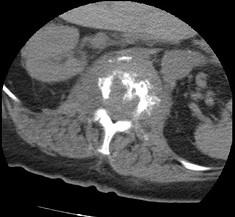

问题 男,67岁,背痛,发热,寒战半月余,有镰状细胞贫血病,请结合影像学检查,选择最可能的诊断 ( )

选项 A、脊髓空洞症 B、脊柱骨髓炎 C、椎体压缩骨折 D、脊柱转移瘤 E、脊柱结核

答案 B